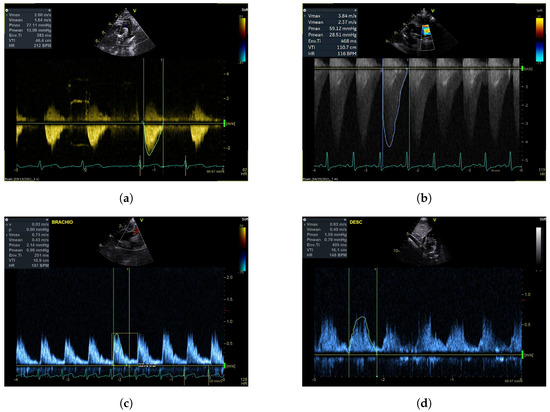

The same plot digitiser was used to determine the number of beats per second, allowing the heart rate of each profile to be determined. The clinicians noted that measuring heart rate directly from the image by measuring the peak-to-peak difference of the cardiac waveforms was a more reliable approach compared to using the value provided in the bottom right-hand corner of the image, as shown in Figure 2. Thus, in images in which the electrocardiogram (ECG) was present—for example, Figure 2a–c—the heart rate was calculated by measuring the time interval between successive peaks of the QRS complex. However, in images such as Figure 2d, in which the ECG was not present, the time interval between the successive peaks of the velocity profiles was used to calculate the heart rate. In both cases, the time intervals between 4–5 successive peaks were measured, and the average was calculated, which was then used as the associated heart rate. We note that this approach introduces human error at the plot digitization stage; however, calculation of the heart rates was then conducted via an in-house Python script. The sampling rate at which the velocity profiles were measured was not available, as this metric did not fall within the clinical protocol when the data were collected. As a result, methods such as using a Fourier transform were not an option. As such, it would not have been possible to find the right scaling for the y-axis.

Figure 2. Sample Doppler TTE images that were used within the study. The images in (ad) show a coarctation measurement post intervention, coarctation measurement pre-intervention, innominate artery measurement post intervention, and descending aorta measurement pre-intervention.